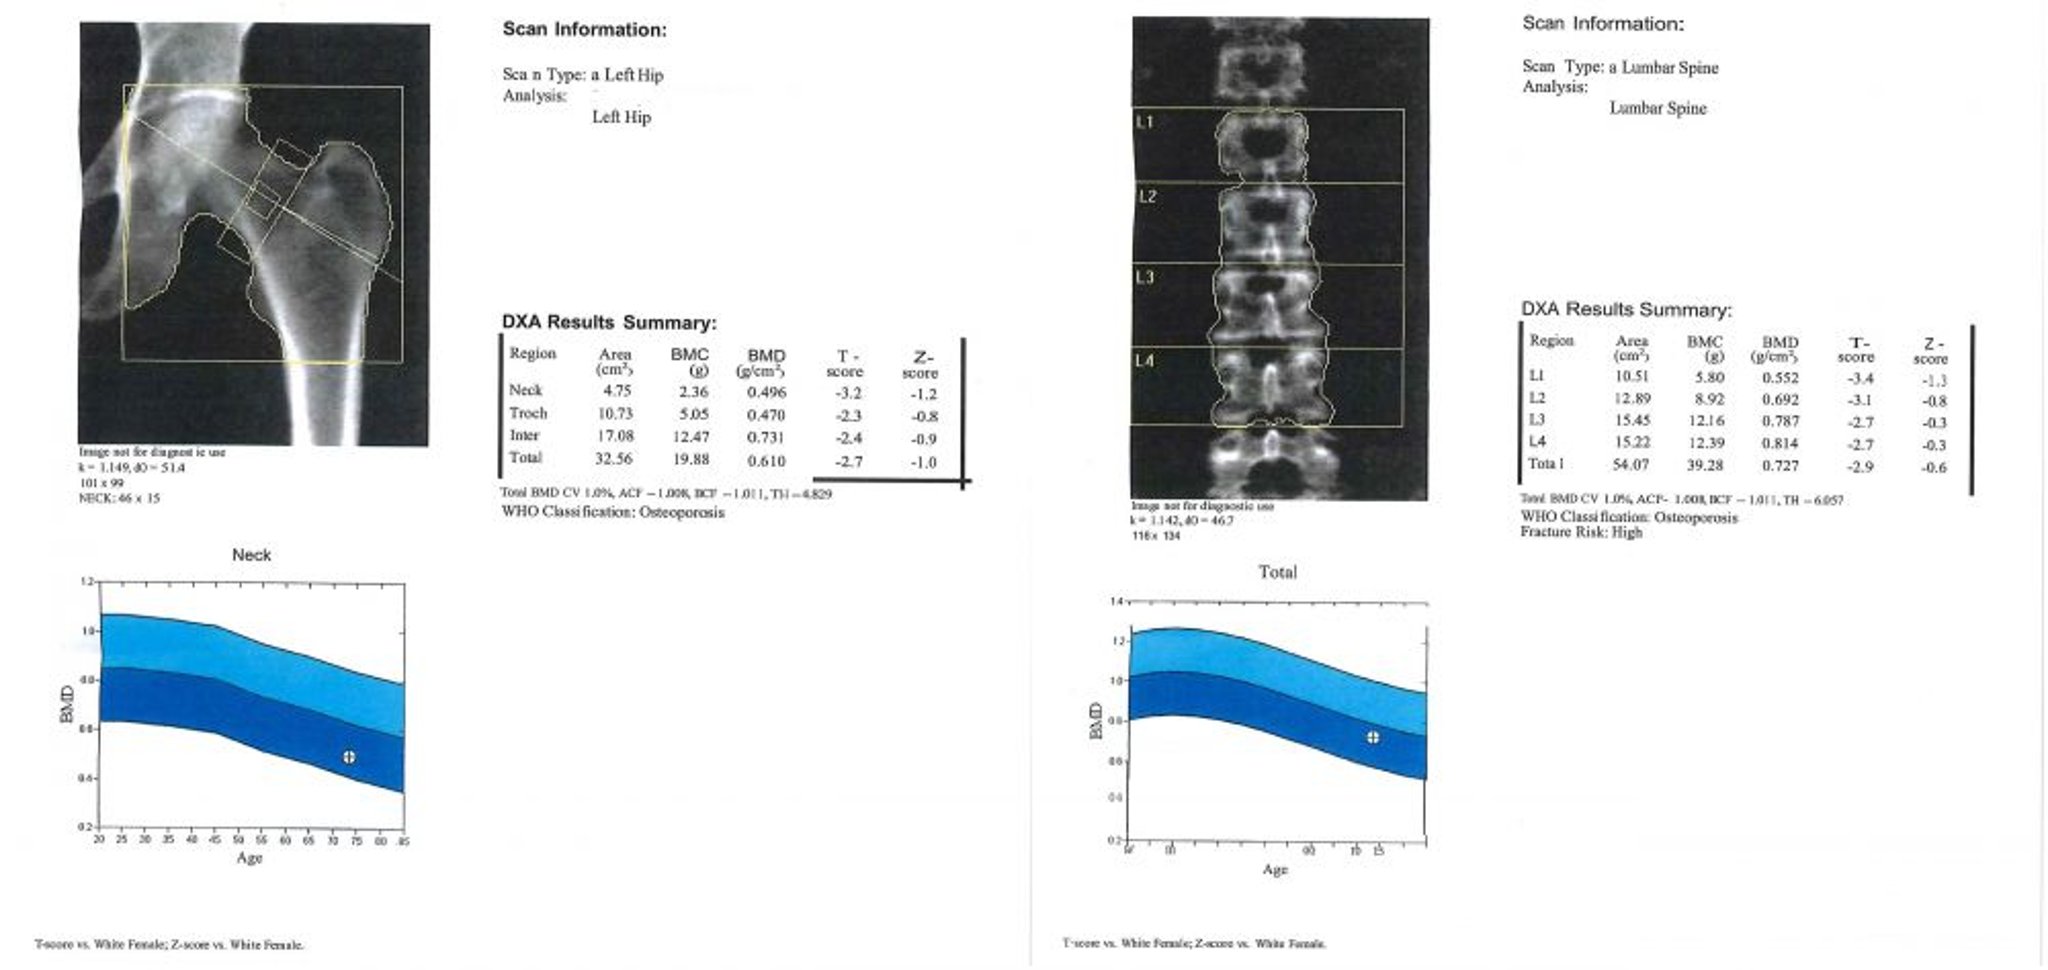

This image is an example of a DXA scan report. In the graph, the area in light blue represents osteopenia and the area in dark blue represents osteoporosis. The patient’s values are represented by the “+” sign inside the circle in each graph.

Image courtesy of Marcy B. Bolster, MD.